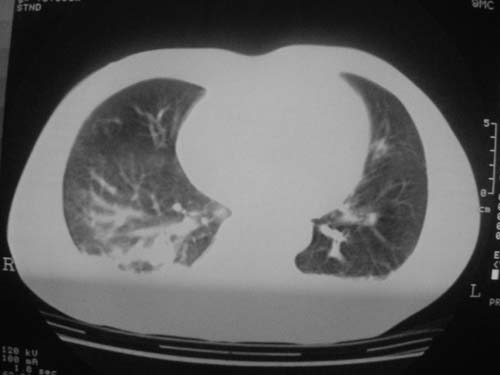

这是第五天拍的ct,纵隔窗我没都传,实在是太费时,请教各位老师,此病人有肺水肿吗?帮忙分析一下